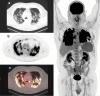

Purpose: [18F]-2-Fluoro-2-deoxy-D-glucose PET/CT (FDG PET/CT) is a sensitive and quantitative technic for detecting inflammatory process. Glucose uptake is correlated with an increased anaerobic glycolysis seen in activated inflammatory cells such as monocytes, lymphocytes, and granulocytes. The aim of the study was to assess the inflammatory status at the presumed peak of the inflammatory phase in non-critically ill patients requiring admission for COVID-19.

Methods: Patients admitted with COVID-19 were prospectively enrolled. FDG PET/CT was performed from day 6 to day 14 of the onset of symptoms. Depending on FDG PET/CT findings, patients' profiles were classified as "inflammatory" or "low inflammatory." FDG PET/CT data were compared with chest CT evolution and short-term clinical outcome. All inflammatory sites were reported to screen potential extra-pulmonary tropism.

Results: Thirteen patients were included. Maximum standardized uptake values ranged from 4.7 to 16.3 in lungs. All patients demonstrated increased mediastinal lymph nodes glucose uptake. Three patients (23%) presented mild nasopharyngeal, two patients (15%) bone marrow, and five patients (38%) splenic mild increase in glucose uptake. No patient had significant digestive focal or segmental glucose uptake. There was no significant physiological myocardial glucose uptake in all patients except one. There was no correlation between PET lung inflammatory status and chest CT evolution or short-term clinical outcome.

Conclusion: Inflammatory process at the presumed peak of the inflammatory phase in COVID-19 patients is obvious in FDG PET/CT scans. Glucose uptake is heterogeneous and typically focused on lungs.